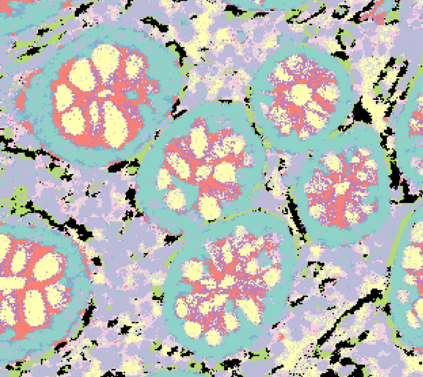

The usage of chemical imaging technologies is becoming a routine accompaniment to traditional methods in pathology. Significant technological advances have developed these next generation techniques to provide rich, spatially resolved, multidimensional chemical images. The rise of digital pathology has significantly enhanced the synergy of these imaging modalities with optical microscopy and immunohistochemistry, enhancing our understanding of the biological mechanisms and progression of diseases. Techniques such as imaging mass cytometry provide labelled multidimensional (multiplex) images of specific components used in conjunction with digital pathology techniques. These powerful techniques generate a wealth of high dimensional data that create significant challenges in data analysis. Unsupervised methods such as clustering are an attractive way to analyse these data, however, they require the selection of parameters such as the number of clusters. Here we propose a methodology to estimate the number of clusters in an automatic data-driven manner using a deep sparse autoencoder to embed the data into a lower dimensional space. We compute the density of regions in the embedded space, the majority of which are empty, enabling the high density regions to be detected as outliers and provide an estimate for the number of clusters. This framework provides a fully unsupervised and data-driven method to analyse multidimensional data. In this work we demonstrate our method using 45 multiplex imaging mass cytometry datasets. Moreover, our model is trained using only one of the datasets and the learned embedding is applied to the remaining 44 images providing an efficient process for data analysis. Finally, we demonstrate the high computational efficiency of our method which is two orders of magnitude faster than estimating via computing the sum squared distances as a function of cluster number.